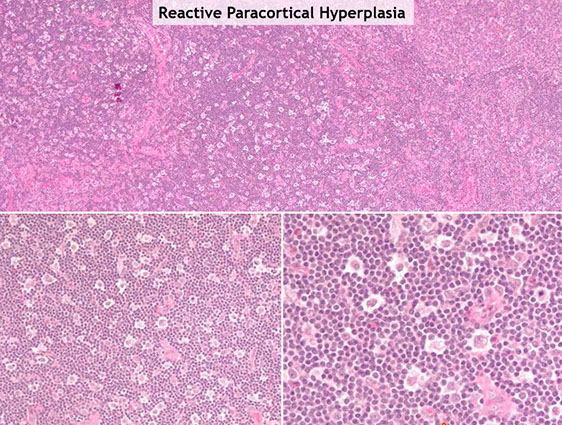

Reactive Paracortical Hyperplasia

Expansion of paracortex from T-cells proliferation, which can be due to drugs, viruses and vaccines

- architecture is preserved

- Immunoblasts in a sea of small T cells and histiocytes (immunoblasts can be CD30+, but this is not Hodgkins!!)

- assoc c viral infx, post-vaccine lymphadenitis, Infectious mononucleosis (EBV), drug-induced hypersensitivity, dermatopathic lymphadenitis, histiocytic necrotizing lymphadenitis, SLE

Micro: T-cells appear monomorphous, small and mature appearing

- have almost evenly-spaced scattered interdigitating dendritic cells sprinkled throughout that gives it a mottled-effect

Reactive paracortical and reactive follicular hyperplasia tend to co-exist

Reactive paracortical hyperplasia [3]. Hyperplasia of the paracortex outside of follicles. Can have vaguely nodular areas of enlargement of the paracortex. The T-cells appear monomorphous, small and mature appearing. Have almost evenly-spaced scattered interdigitating dendritic cells sprinkled throughout that gives it a mottled-effect